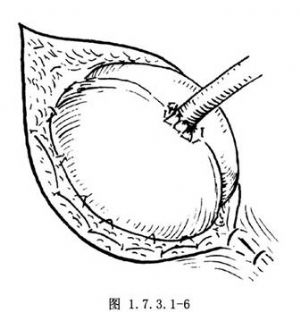

6.如估计用上述方法不能满意地解除梗阻,准备术后切开盲肠减压时,可将腹壁切口的壁层腹膜与皮肤的真皮层行间断缝合(图1.7.3.1-6)。最后,将盲肠的浆肌层与壁层腹膜缝合,以此缝线结扎凡士林纱布条(图1.7.3.1-7)。最后用凡士林纱布覆盖。